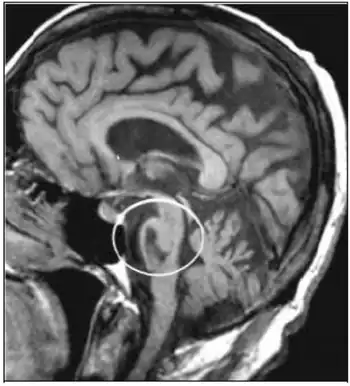

| Locked-in syndrome can be caused by a stroke at the level of the basilar artery denying blood to the pons, among other causes. | |